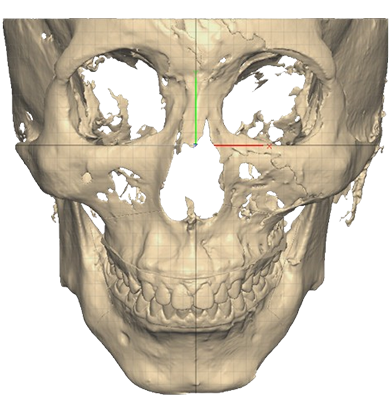

STEP 01

Cutting guide를 이용하여 3D로 계획된 삭제량만큼 뼈를 삭제

STEP 02

Wafer를 이용해 상악의 돌출을 뒤로 교정 무턱의 하악을 앞으로 빼내어 정상교합에 위치시킨 뒤, 맞춤형 Plate로 뼈를 고정

수술결과

무턱 개선 : 턱 끝 기준 17mm 전진